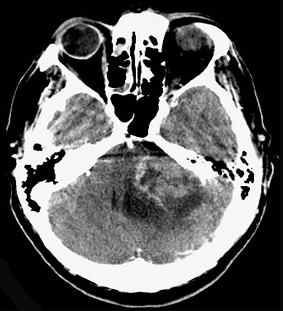

后颅窝占位听神经瘤

图片尺寸1096x1284